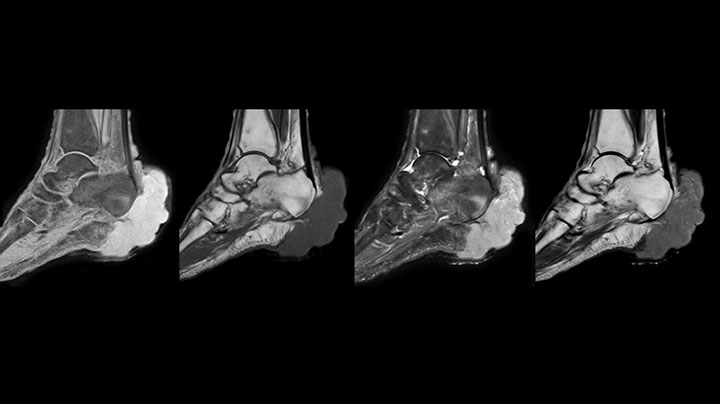

mDIXON TSE of ankle

MRI examination on Prodiva 1.5T of a 72-year-old female with a malignant melanoma in the ankle. mDIXON TSE provides excellent fat

suppression, without the distortion that is often seen at such extremities.

mDIXON TSE of ankle melanoma